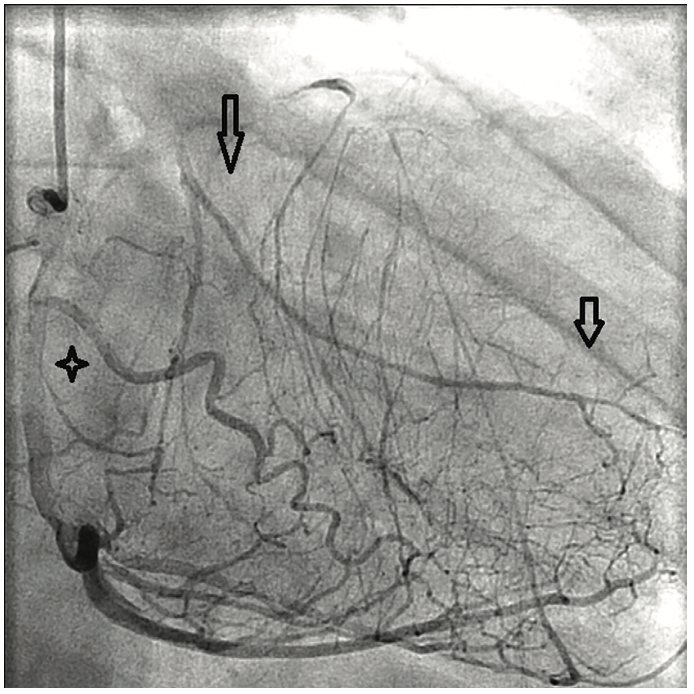

Angiographic findings of atherosclerotic disease and stenosis in the left main coronary artery are not uncommon in both symptomatic and relatively asymptomatic patients. However, the angiographic finding of a completely occluded left main coronary artery is relatively uncommon and most often not compatible with life.1,2 It is even more unusual to have no symptoms related to the complete obstruction of the left main coronary artery.

Left main coronary artery stenosis to a varying degree is not an uncommon finding on coronary angiography in patients with known and unknown coronary artery disease. Several reports and studies have been published pertaining to clinical presentation and management of left main coronary artery stenosis, but very little is known about the clinical presentation or incidence of left main coronary artery occlusion. This is likely due to total occlusion of the left main coronary artery being incompatible with life. Total occlusion of the left main coronary artery is usually a highly symptomatic event or in many cases, a terminal event. The survival rate and clinical symptoms are likely correlated with the rate of occlusion and the degree of collateralization from the right coronary artery that can supply blood flow to the left coronary arteries when the left main coronary artery becomes totally occluded.